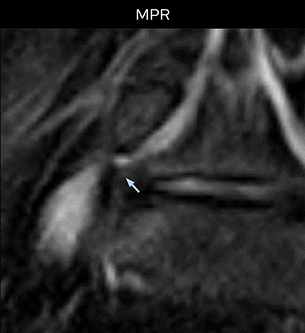

Good spatial resolution is required

“For both brachial and lumbar plexus, we are currently using a 230 mm FOV and voxels of about 1 x 1 x 2 mm acquired (1 x 1 x 1 mm reconstructed). This provides us a good representation of the nerves, even though this FOV is relatively small. Regarding the inplane resolution, we hope to be able to bring that down to 0.7 mm, similar to our typical 2D multislice T2W images,” says Tanji.

“Recently, the two surgical methods extreme and oblique lateral interbody fusion (XLIF and OLIF) have become mainstream for minimally invasive treatment of lumbar spinal canal stenosis and intervertebral foramen stenosis. With these surgical techniques, the spine is approached from the flank, and prior knowledge of the exact anatomy of the lumbosacral plexus would be extremely helpful. To that end, high slice resolution (less than 1 mm acquisition) that enables sharper sagittal MPR images will be needed.”